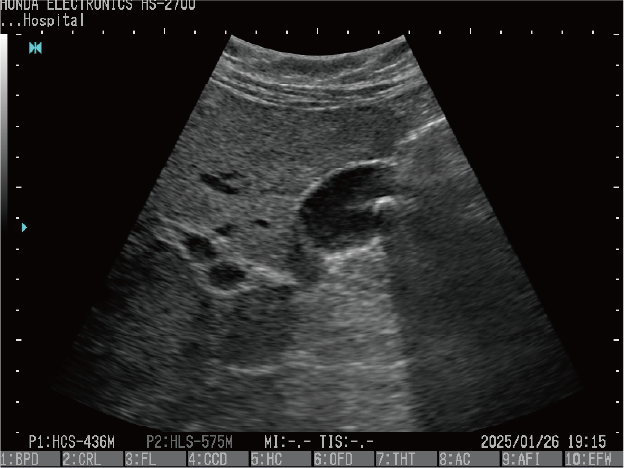

腎臓